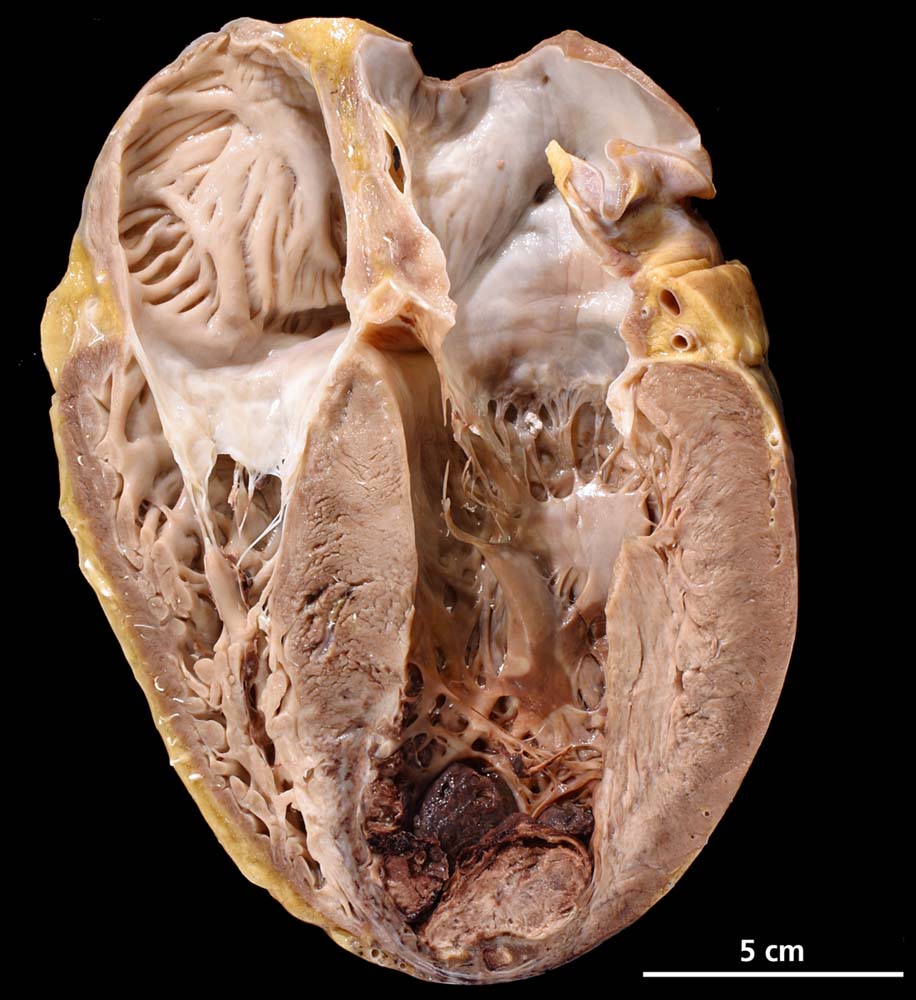

Subakuter antero-apiko-septaler Myokardinfarkt mit Wandthrombose

Endokardfibrose des linken Vorhofes. Ausgeprägte, biventrikuläre exzentrische Myokardhypertrophie. Ausgedehnter subakuter antero-apiko-septaler Myokardinfarkt mit Aneurysma apikal und grossem wandhaftendem Thrombus.

Seröser Perikarderguss (60 ml). Dilatation beider Vorhöfe. Endokardfibrose des linken Vorhofes. Myokardinfarktnarbe im Bereich der Hinterwand. Schwere stenosierende Koronarsklerose aller drei Hauptäste mit subakuten thrombotischen Verschlüssen der rechten Koronararterie und im Ramus interventricularis anterior.

Adipositas, Nikotinabusus, Diabetes mellitus II. Spitaleintritt wegen zunehmender Dyspnoe und Aszites. Verdacht auf stumm verlaufenden Vorderwandinfarkt bei Hypokinesie. Ejektionsfraktion 25 %. Mitral- und Trikuspidal- und biventrikuläre Herzinsuffizienz. Tot im Bett aufgefunden.